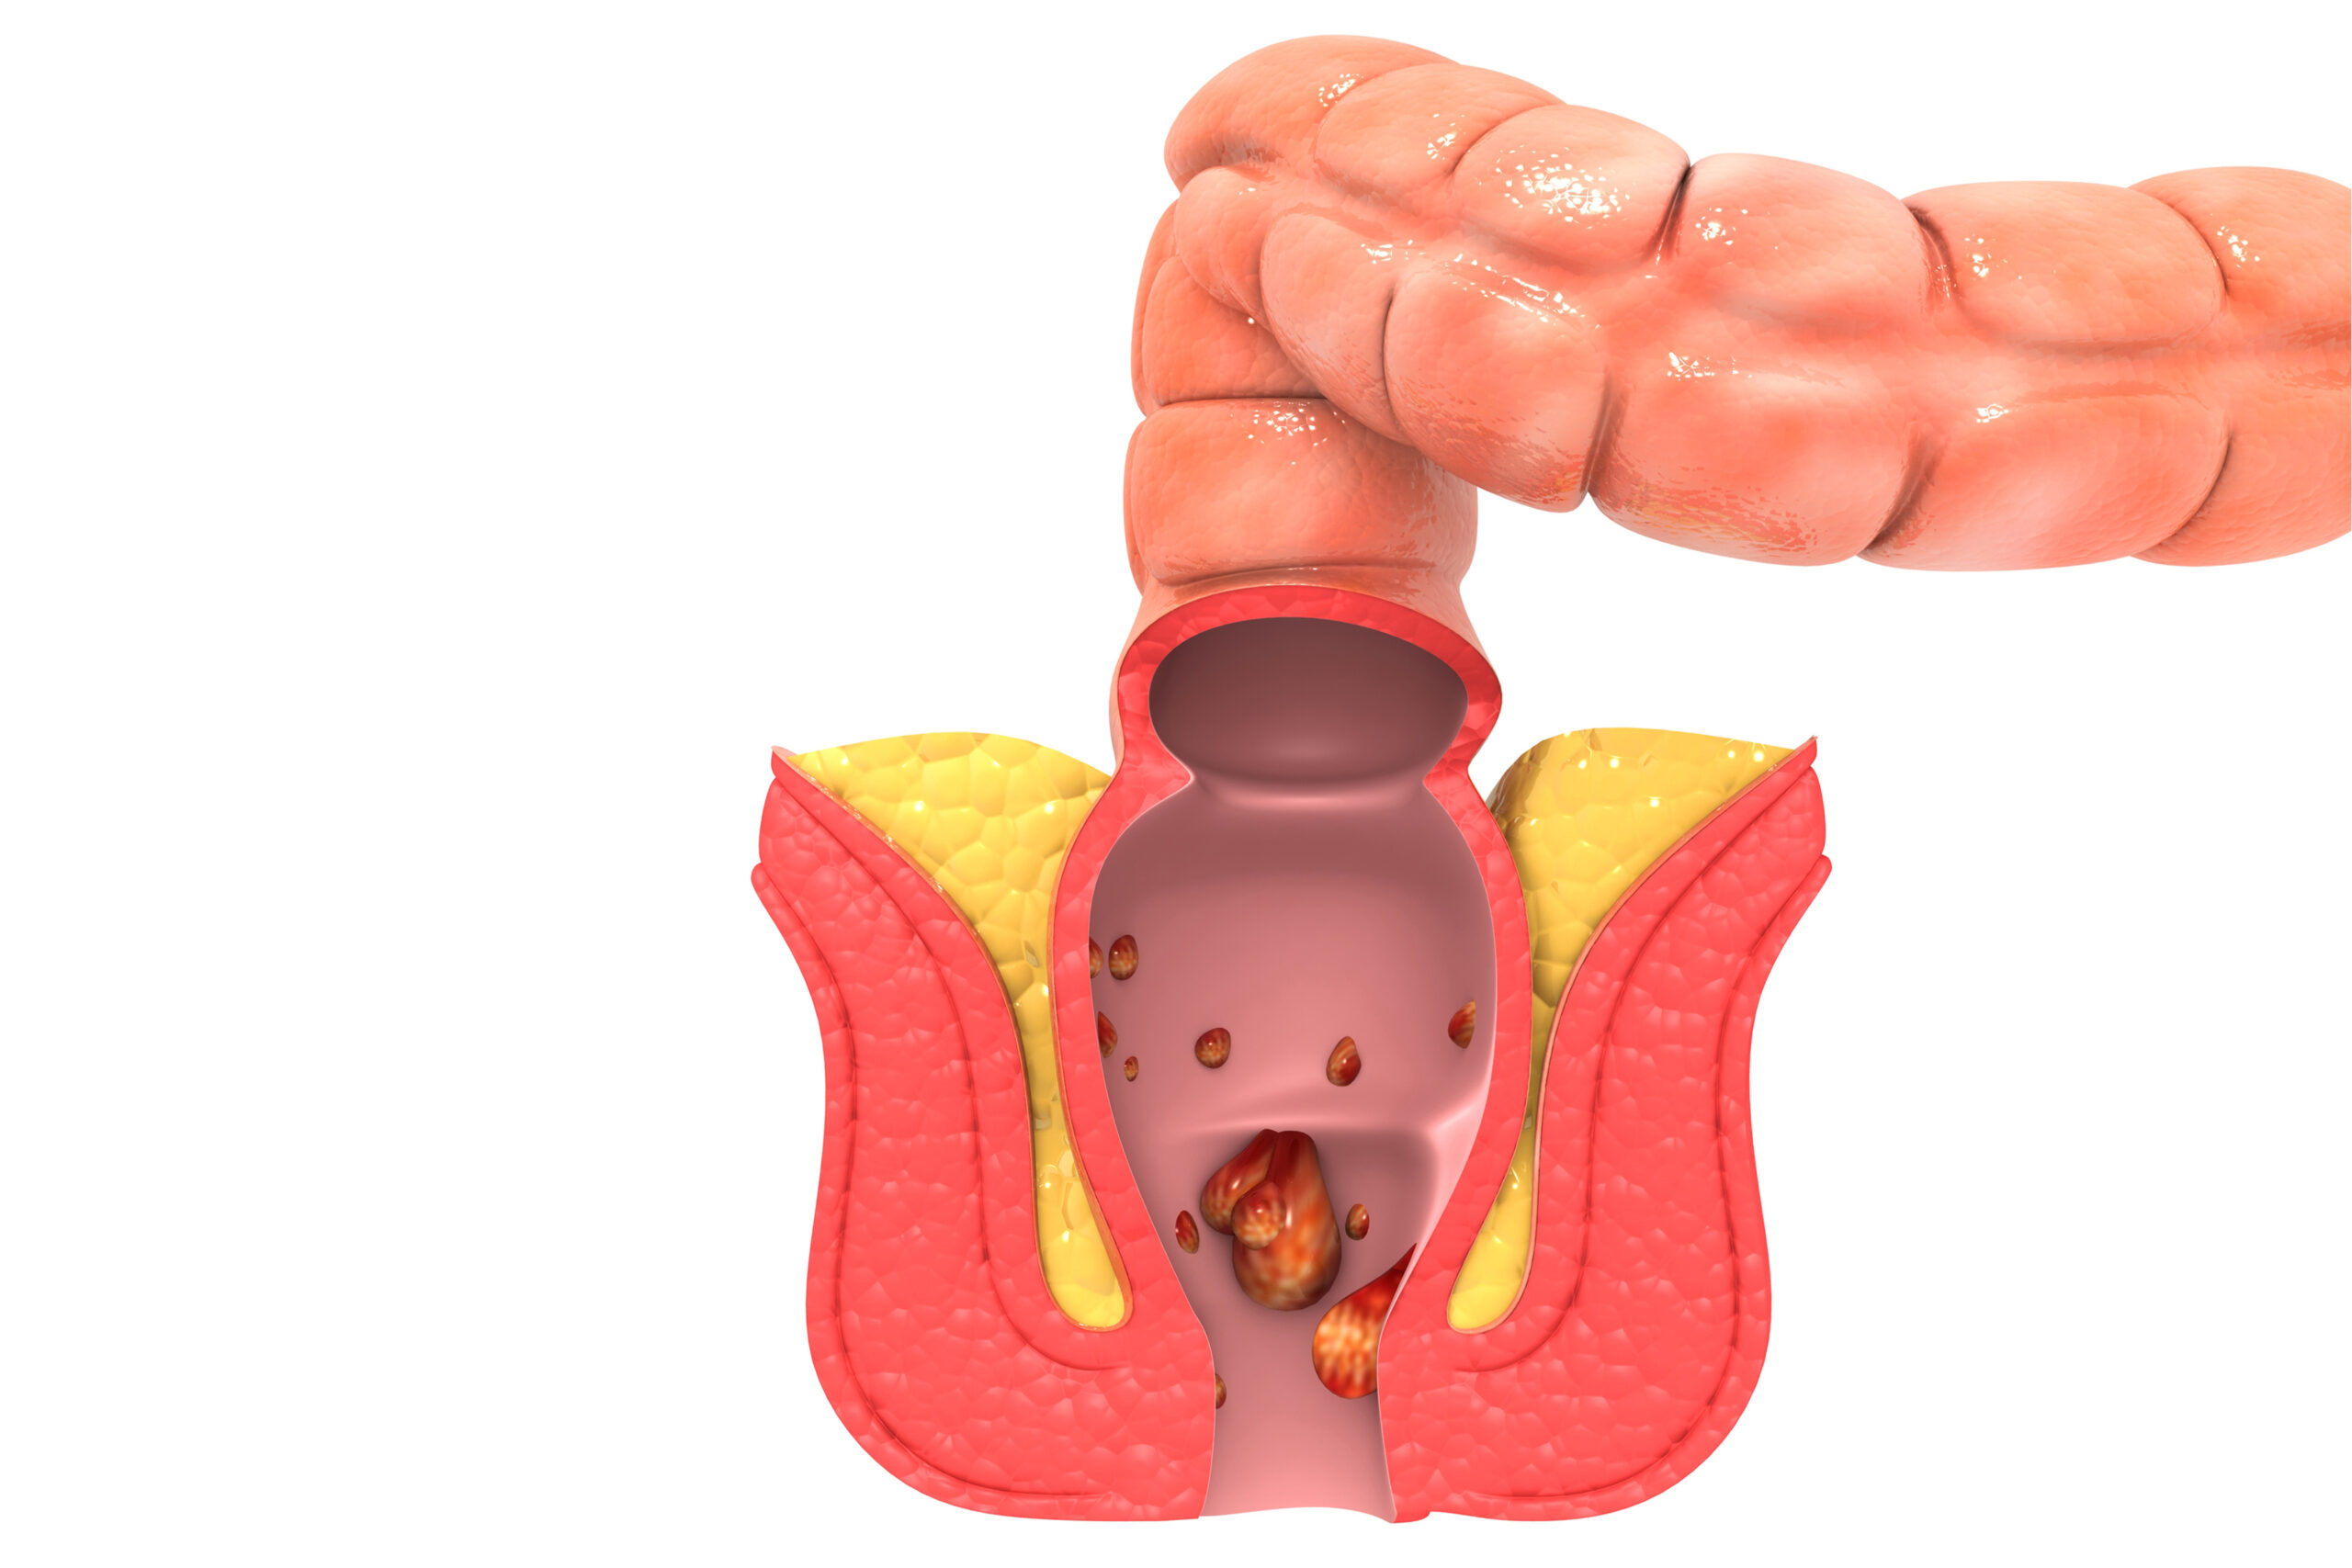

Το παχύ έντερο που καταλήγει στον πρωκτό και οι αιμορροΐδες

Εξωτερικές αιμορροΐδες σχηματίζονται στο εξωτερικό του πρωκτού. Τα συμπτώματα μπορεί να περιλαμβάνουν:

- φαγούρα γύρω από τον πρωκτό

- οδυνηρά, σκληρά εξογκώματα κοντά στον πρωκτό

- πόνος στον πρωκτό ή πόνο που επιδεινώνεται όταν κάθεστε